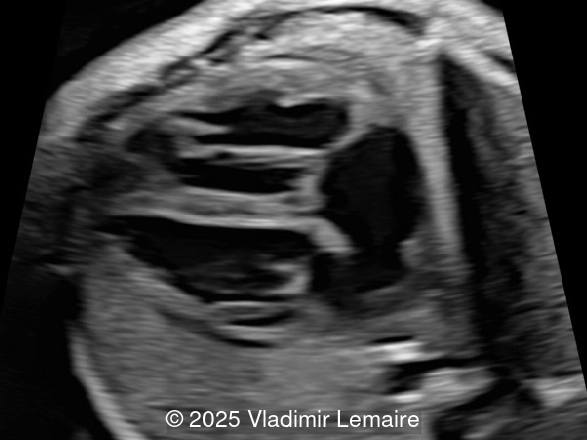

STIC of the transverse aortic arch view with color Doppler coupled with volume contrast imaging (VCI-A). Note the presence of the dilated aorta.

Image 5 STIC of the transverse aortic arch view with color Doppler coupled with volume contrast imaging (VCI-A). Note the presence of the dilated aorta.